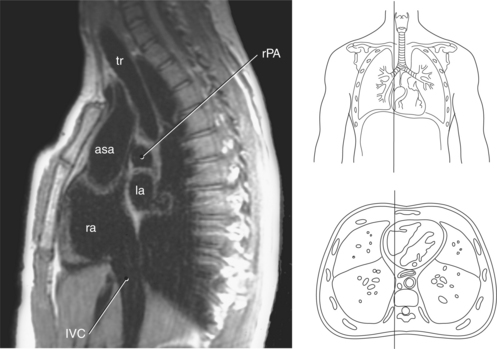

Figure 6.60 Sagittal, T1-weighted MR scan with aortic arch and descending aorta.

Key: ar, aortic arch; da, descending aorta; mbr, mainstem bronchi; rPA, right pulmonary artery; ab, aortic bulb; la, left atrium; rv, right ventricle.

Figure 6.75 Sagittal, T1-weighted MR scan of inferior vena cava.

Key: tr, Trachea; rPA, right pulmonary artery; asa, ascending aorta; la, left atrium; ra, right atrium; IVC, inferior vena cava.